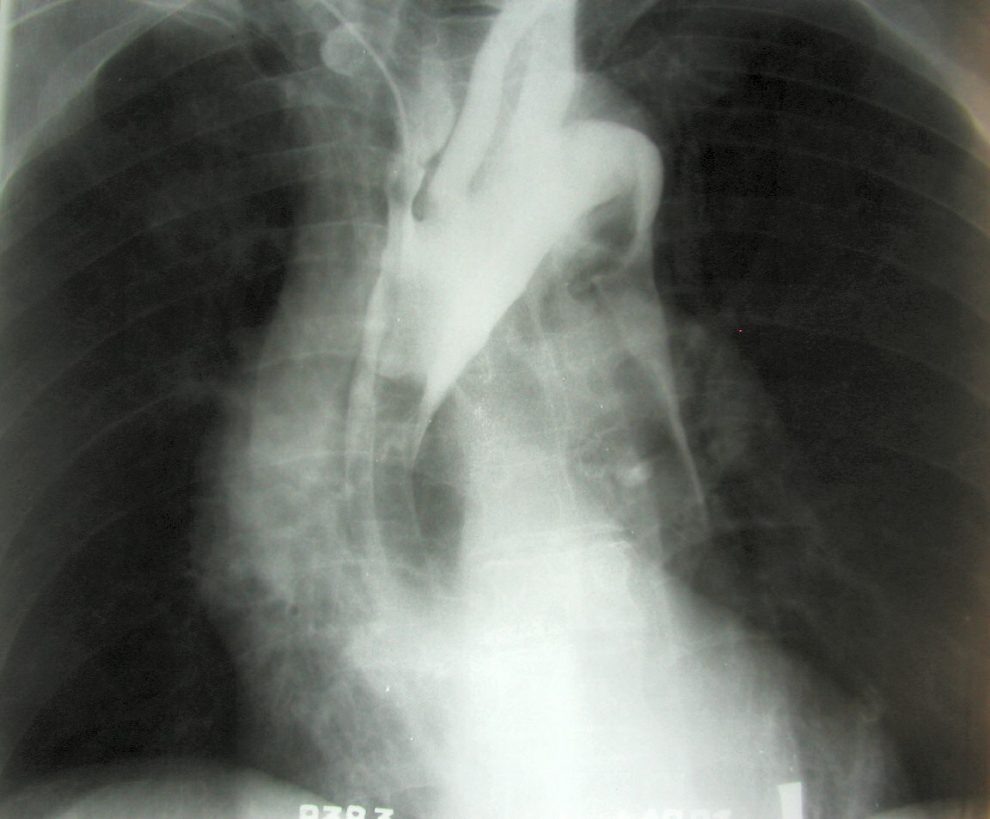

Definiția pe scurt a anevrismului cerebral este următoarea: dilatarea unei porțiuni dintr-un vas de sânge și umflarea zonei respective, ce apare ca urmare a slăbirii peretului acestuia.

Medicii spun că anevrismele cerebrale sunt de două feluri: rupte sau nerupte. ”Fisurarea unuia poate să apară în unele cazuri, ducând la o sângerare minimă, care favorizează apariția unei dureri de cap la fel de intensă ca și cea provocată de ruptura anevrismală. Aproape întotdeauna, fisurarea unui anevrism este urmată de o ruptură masivă a acestuia“, spune dr. Sofia Nistor.